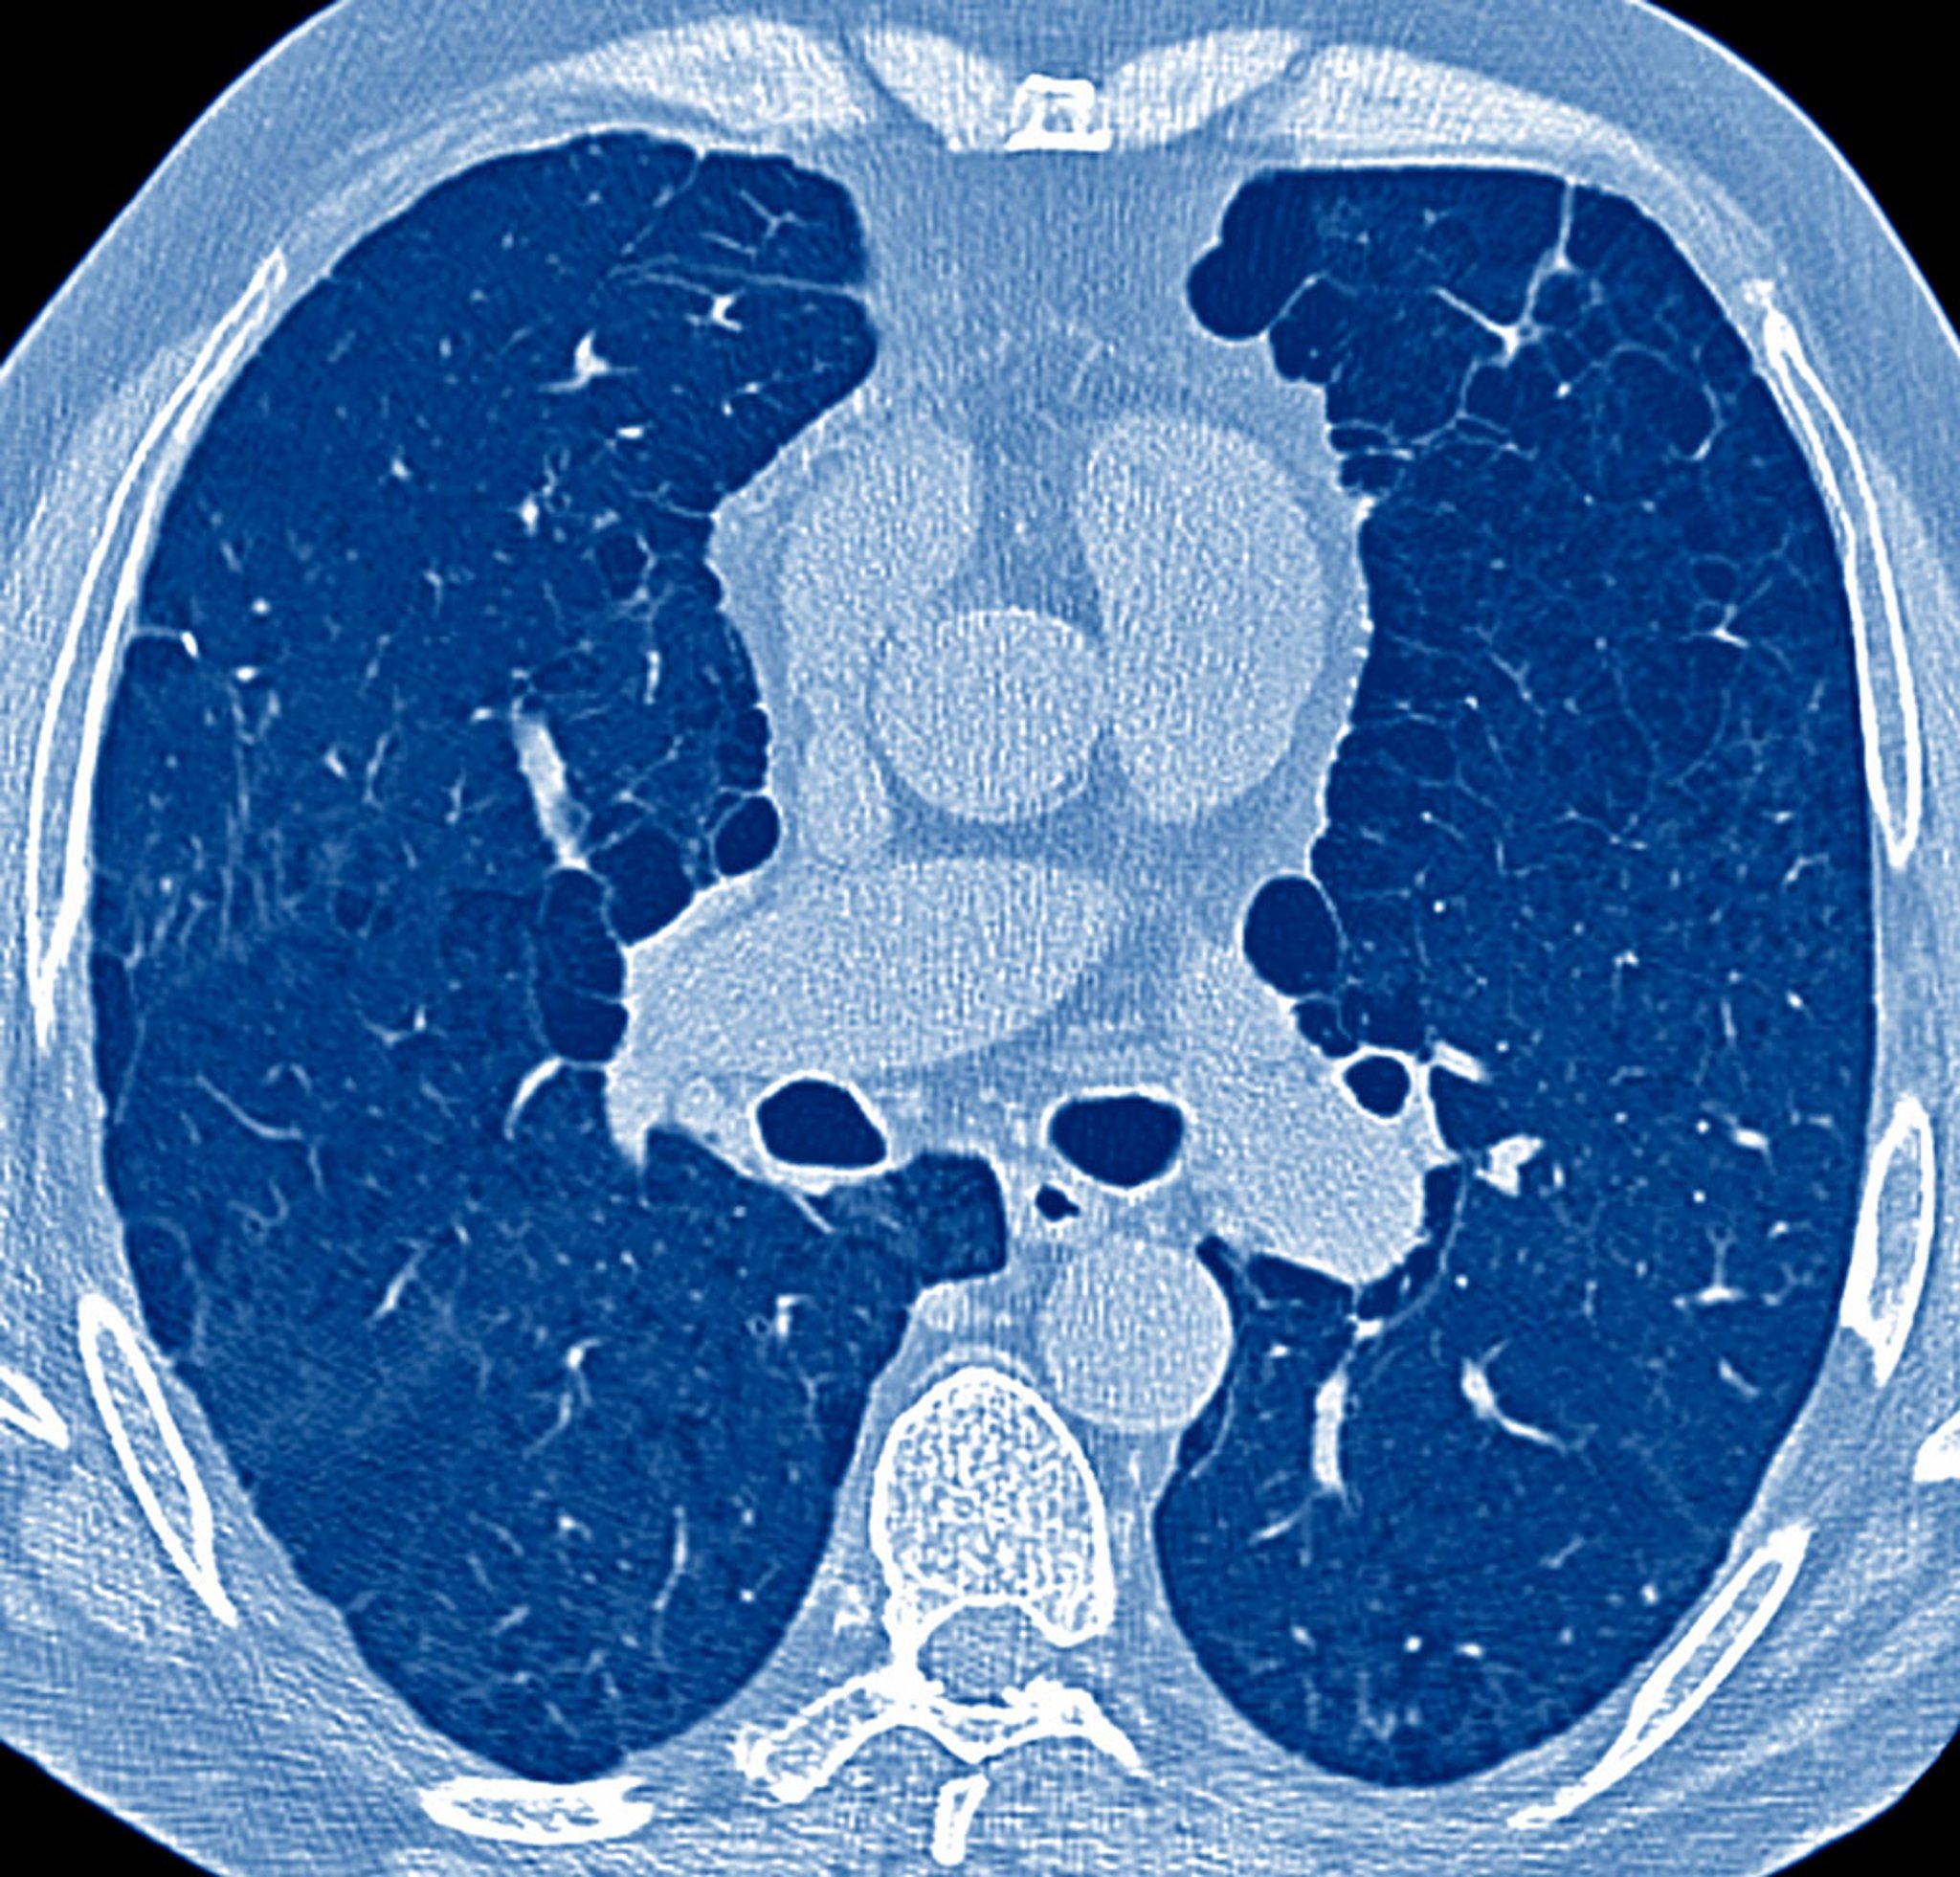

呼吸系统疾病患者的评估的关键在于病史采集、体格检查,以及在多数情况下进行胸片检查。这些组件确定了后续测试的必要性,其中可能包括 肺功能测试动脉血气(ABG)分析胸部CT 和其他 胸部影像学检查超声心动图6分钟步行测试心肺运动测试右心导管检查支气管镜检查以及肺活检。